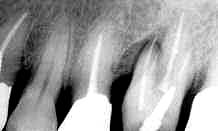

図32.術前 図33.術直後 図34.術後1年

【症例4】(図35〜45)

患者:67歳、男性

初診:1982年8月18日

診断:成人性歯周炎

所見:全歯において歯石沈着が著明で、口腔清掃状態も良好とはいえないが、年齢のわりに歯牙、

歯周組織ともに堅固である。6│6に骨欠損を認めるが臨床症状はない。。

処置:上下前歯部FOp施行予定とし同部の抜髄および全顎にわたるPcurを行う。

・76│ 1984年1月23日 FOp(HAP使用せず)

・6│  1985年6月26日 口蓋根ヘミセクション

・│6  1988年3月23日 FOp+アクトセラムK補填

図35.初診時(1982年8月) 図36.初診後6年9ヵ月(1989年5月)

図37.│6術前5年4ヵ月 図38.初診以来、年1回のメインテナンスを

行っていたが、5年間にわたる歯周

疾患の進行が認められる

図39.│6術後1年

図40.│6術中。X線では予測できなかった口蓋

側の骨欠損を見ることができる

図41.│6術後1週。HAPを使用した場合、術直後の

創面は美しくないが、掻爬が完全であれば、

必ず良好な経過を見る。

図42.│6術後1年